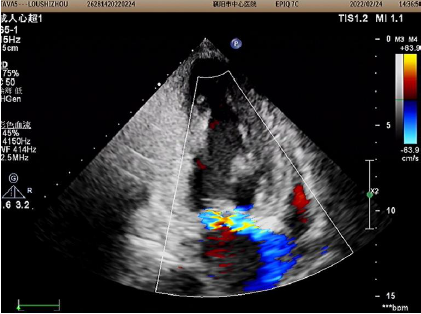

心脏彩超

2022年2月24日术后超声图像

术后改善明显:

主动脉瓣峰值流速从4.59M/s降至2.12M/s;

平均跨瓣压差从84mmHg降至18mmHg;

升主动脉内径从55mm降至52mm

左室射血分数EF值从46%升至52%